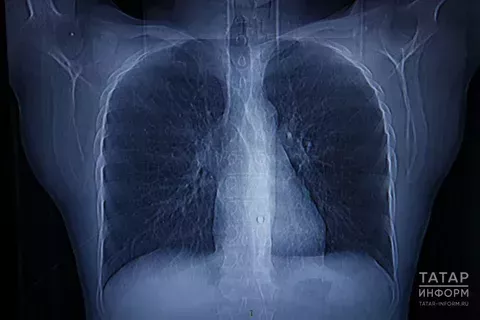

24 мартта Бөтендөнья туберкулезга каршы көрәш көне билгеләп үтелә. Иң куркынычлардан саналучы авыру дөньяда үлемгә китерүче 10 төп сәбәпнең берсе булып тора

– Туберкулез таякчыклары бөтен органнарны да: бөерне, бавырны, умыртка баганасын, баш миен һәм башка органнарны зарарларга мөмкин. Бер тапкыр туберкулез белән авырып, терелгән кеше әлеге авыруны кабат эләктерә ала, – ди район хастаханәсенең фтизиатр бүлмәсе шәфкать туташы Нәргизә Бәдертдинова. – Узган ел туберкулез ачыкланган 2 кеше исәпкә куелды. Районда туберкулез белән 10 кеше исәптә тора. Аларның барысы да – 40 яшьтән узган өлкәннәр. Бу соңгы чик, дип әйтеп булмый, чөнки кеше туберкулез белән авыруын белмәскә дә мөмкин. Шуңа 15 яше тулган яшүсмерләр һәм өлкәннәр елга бер тапкыр флюорография узарга тиеш. Флюорография туберкулез, үпкә ялкынсынуы, яман шеш кебек куркыныч авыруларны ачыкларга ярдәм итә. Шунысы сөендерә: районда туберкулез белән авыручы балалар юк.

– Туберкулез микроблары, авыру сөйләшкәндә, йөткергәндә, төчкергәндә, көлгәндә, төкерек белән һавага тарала һәм шул ук һаваны сулаучы сәламәт кеше организмына үтеп керә. Авыру башлану өчен берничә сәбәп кирәк: тумыштан килгән түбән иммунитет, тиешенчә тукланмау, еш салкын тию, бронхиаль астма, хроник бронхит, беренче һәм икенче төр шикәр авыруы, даими стресслар, аракы, тәмәке һәм наркотиклар куллану. Туберкулез белән авыручыларны ачыклау максатында, район үзәк хастаханәсе ел дәвамында нәтиҗәле эш алып бара һәм кисәтү чаралары да үткәрә. Авыру расланган кешеләр махсус диспансерларга дәваланырга җибәрелә, – ди Нәргизә Бәдертдинова.

Республиканың 15 рай-онында туберкулез белән авыручылар саны республика күрсәткеченнән югары. Бу исемлектә Югары Ослан, Спас, Сарман, Яңа Чишмә, Яшел Үзән, Нурлат, Минзәлә, Менделеевск, Бөгелмә һәм тагын алты район бар. Биш районда туберкулез белән авыручылар саны 1,5 мәртәбә арткан. Исемлектә Мөслим районы юк, әмма тынычланырга ярамый. Туберкулезга каршы көрәштә иң мөһиме – һәр кешенең үзенең һәм тирә-юнендәгеләрнең сәламәтлеге өчен җаваплылык тоюы, авыруны башлагыч чорында ачыклау өчен елга бер флюорография узу, сәламәт яшәү рәвешен пропагандалау. Үзебезнең һәм якыннарыбызның сәламәтлегенә игътибарлы булыйк!